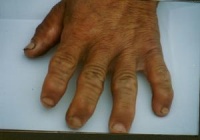

⑴关节增粗:最多见的是多发性、对称性指间关节增粗,常先出现在第二、三、四指的第一指间关节。一般右手指关节增粗比左手明显,受机械损伤的关节或妇女带顶针的指关节增粗较重。

⑹短指(趾)畸形:指节发育比常人短,手小形方。或因各指(趾)发育障碍程度不同,其长短失去正常互相间的比例关系。

本病病情发进展以后,除关节疼痛等早期表现继续加重外,主要有以下症状体征出现:⑴、关节增粗:最多见的是多发性、对称性指间关节增粗,常先出现在第二、三、四指的第一指间关节。一般右手指关节增粗比左手明显,受机械损伤的关节或妇女带顶针的指关节增粗较重。

⑹、短指(趾)畸形:指节发育比常人短,手小形方。或因各指(趾)发育障碍程度不同,其长短失去正常互相间的比例关系。